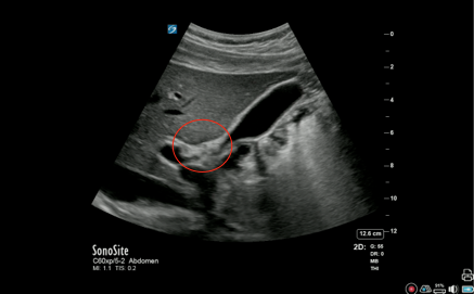

Gallbladder Main Lobar Fissure Image

Circled: Main Lobar Fissure (MLF)